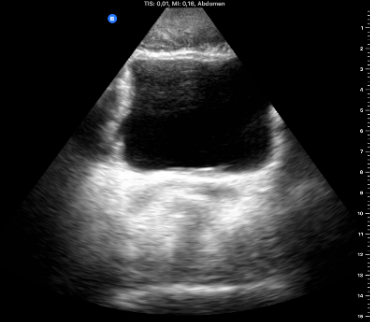

Reconsulta por febrícula y oliguria con coágulos 1 semana después de la RTU-V. Tras ecoscopia anodina en ambulatorio (vejiga sin alteraciones, ambos riñones sin datos de obstrucción), derivación a urgencias y tratamiento con Cefixima 200 mg cada 12 horas. Posterior urocultivo negativo.

Tras el tratamiento quirúrgico, descartó datos de alarma ante clínica obstructiva y fiebre. Aunque habría que haberle derivado a urgencias igualmente para lavado.